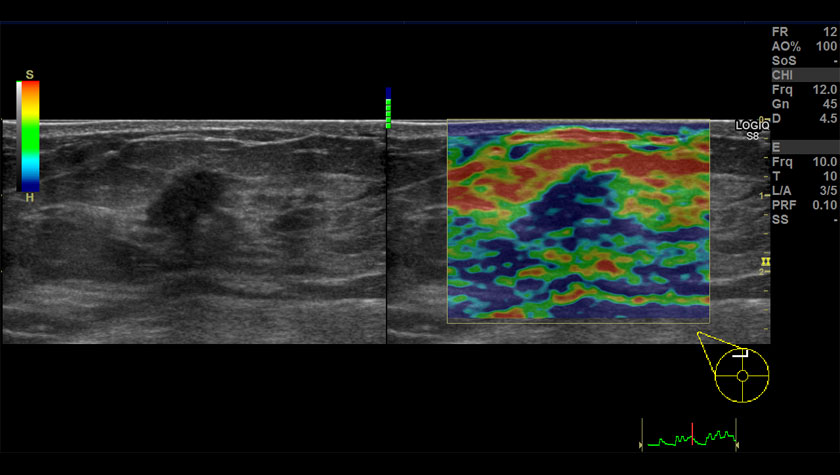

- Elastography Quantification — Количественная эластография;

- Elastography — Эластография;

Щитовидная железа, 2D-эластография сдвиговой волны

Щитовидная железа, датчик L3-12-D

Эластография молочной железы, датчик ML-6-15-D